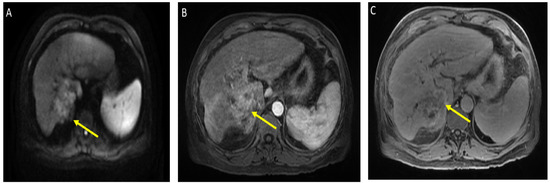

The patient received a total of 6 cycles of atezolizumab 1200 mg intravenously plus a total of 5 cycles of bevacizumab 15 mg/kg (missed one cycle of bevacizumab) given on day 1 of a 21-day cycle. Therapy was then held for two months prior to evaluation for OLT. Follow-up MRI 8 weeks after treatment showed a significant interval treatment response with shrinkage of the segment 7 tumor, as seen in Figure 2. Additional imaging follow-up at 6 months showed post-treatment atrophy of the right lobe of the liver, stable non-enhancing segment 7 mass (LR-TR non-viable); with a new 8 mm lesion in segment 2 of the liver (LI-RADS 4 for arterial enhancement, washout, and size less than 10 mm), as can be seen in Figure 3. PET/CT scan showed no metabolic uptake in the right hepatic lobe with suspected inflammatory uptake in the common bile duct. No bone metastases were appreciated in the bone scan.

Figure 2.

Magnetic resonance imaging of the abdomen. Cirrhosis, splenomegaly, and ascites were noted. Significant interval treatment response. Segment 7 mass has decreased in size (now 3.3 × 3 cm). (A) Diffusion-weighted imaging (DWI): decreased diffusion restriction of seg 7 mass; (B) (arterial)/(C) (delayed) T1 post-contrast imaging: mass is now hypovascular (captured at the follow-up visit, and 8 weeks after the atezolizumab plus bevacizumab started).